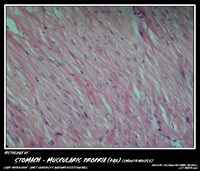

STOMACH